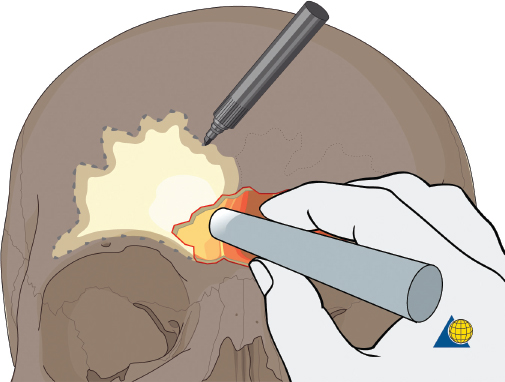

More severe injuries involving the anterior and/or posterior table(s) may require sinus obliteration. The exposure has been described above (open reduction and internal fixation). It is important to maintain a viable pericranial flap that can be used for dural repair if necessary. After complete exposure of the frontal bone (and orbital rims as necessary), all anterior table bone fragments should be carefully removed and kept moist on a side table. It is helpful to maintain the orientation of the fragments with a drawing to assist with re-orientation during the final repair ( Fig. 63.35 ). It is often necessary to complete the frontal sinusotomy, and remove any remaining anterior table bone to visualize the entire sinus. Intraoperative navigation can be useful to define the margins of the sinus. Alternatively, one tine of a bipolar cautery can be placed through a defect in the anterior table and walked around the periphery of the sinus. The outer tine is used to mark the outline of the sinus externally ( Fig. 63.36 ). Transillumination can also be used to outline the sinus. A light source is placed within the sinus, illuminating the periphery, which is then marked in a similar fashion ( Fig. 63.37 ). After the limits of the sinus have been marked, several microplates are pre-applied across the proposed osteotomy sites ( Fig. 63.38 ), maintaining the precise location of the bone flap at the completion of the procedure. The plate is rotated superiorly and the osteotomy is performed ( Fig. 63.39 ). The author prefers a high-speed Midas Rex drill (Medtronic, Inc.) and a B-1 bit. The same tool can be used to make perforations along the periphery of the sinus ( Fig. 63.40 ), and complete the osteotomy by joining the perforations with side cutting capabilities ( Fig. 63.41 ). The osteotomy line should be angled toward the sinus cavity to avoid intracranial penetration ( Fig. 63.42 ). The orbit rims and glabella can be osteotomized with either the drill or osteotomes depending on the degree of preexisting comminution; however, the surgeon must protect the supratrochlear and supraorbital neurovascular pedicles. Finally, an osteotome is inserted through the superior saw kerf and used to break down any intersinus septations, and bone flap is removed ( Fig. 63.43 ).